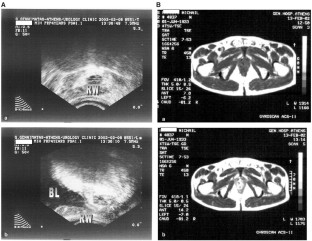

Remzi M et al. Color Doppler Transrectal Ultrasound (TRUS), time to recurrence, and PSA density do replace biopsies in detecting local recurrence following radical prostatectomy. J Urol 2003; 169 (Suppl): 299.

Kramer S et al. Sensitivity of computed tomography in detecting local recurrence of prostatic carcinoma following radical prostatectomy. Br J Radiat 1997; 70: 995–999.

Anagnostou T et al. Magnetic resonance using body coil and enhanced spin echo sequence imaging in evaluating local recurrence following radical prostatectomy. Eur Urol 2003; 2: 22 (78).